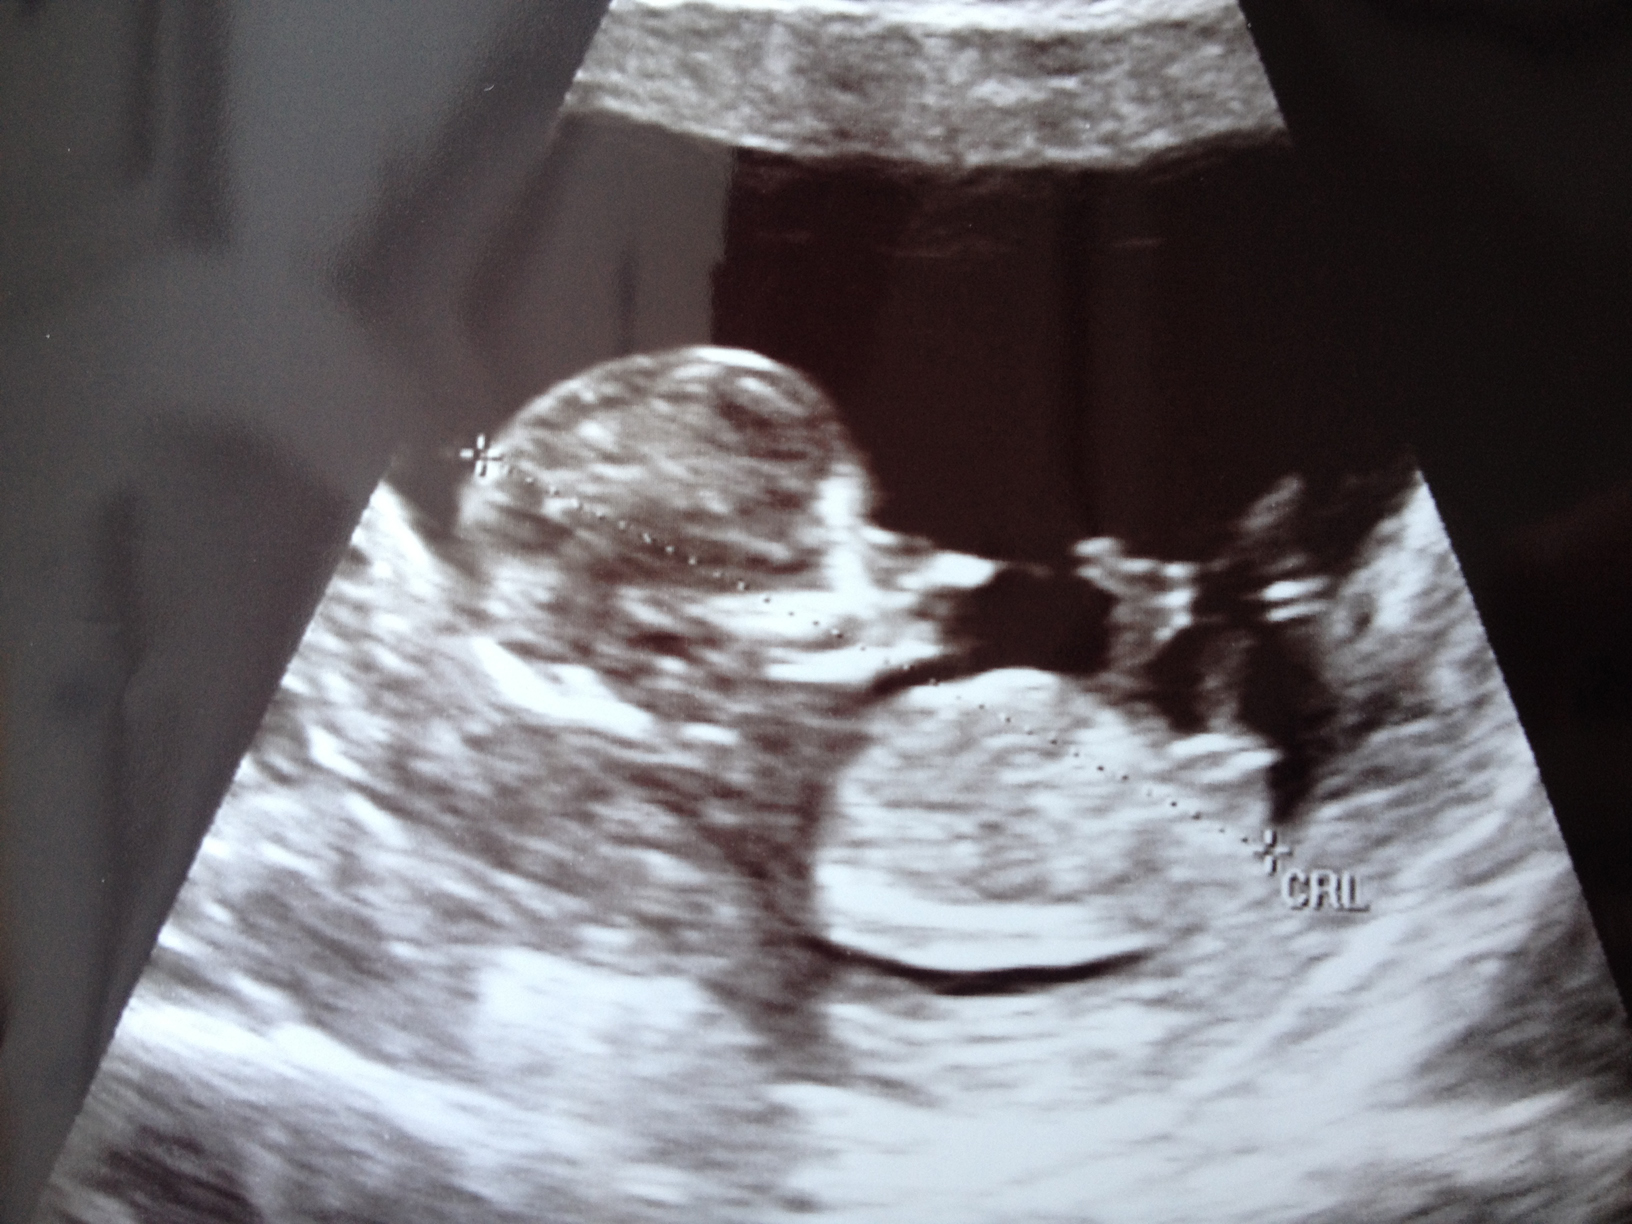

Maybe girl!!! GL what are you hoping for?

girl lean.

Hmmm. Baby is really curled. But nub looks girly in current position. I would lean girl.

I'm going girl guess

Im going girl on this one too x

Thanks everyone! We go in for an elective US in 2 week. I will be 16w 3d, hopefully we will be able to tell then!